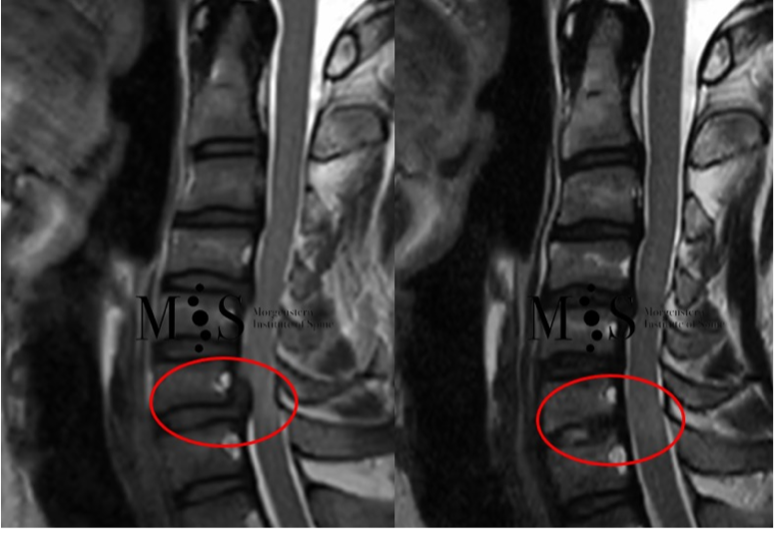

Realitzada amb èxit la primera cirurgia endoscòpica a Espanya per solucionar la compressió medul·lar cervical

Mitjançant un abordatge endoscòpic, dut a terme per cirurgians del Morgenstern Institute of Spine del Centre Mèdic Teknon, és possible intervenir una columna cervical amb una incisió a la pell de menys d'1 cm de longitud i una recuperació immediata, i aconseguir l'alta hospitalària a menys de 24 hores.